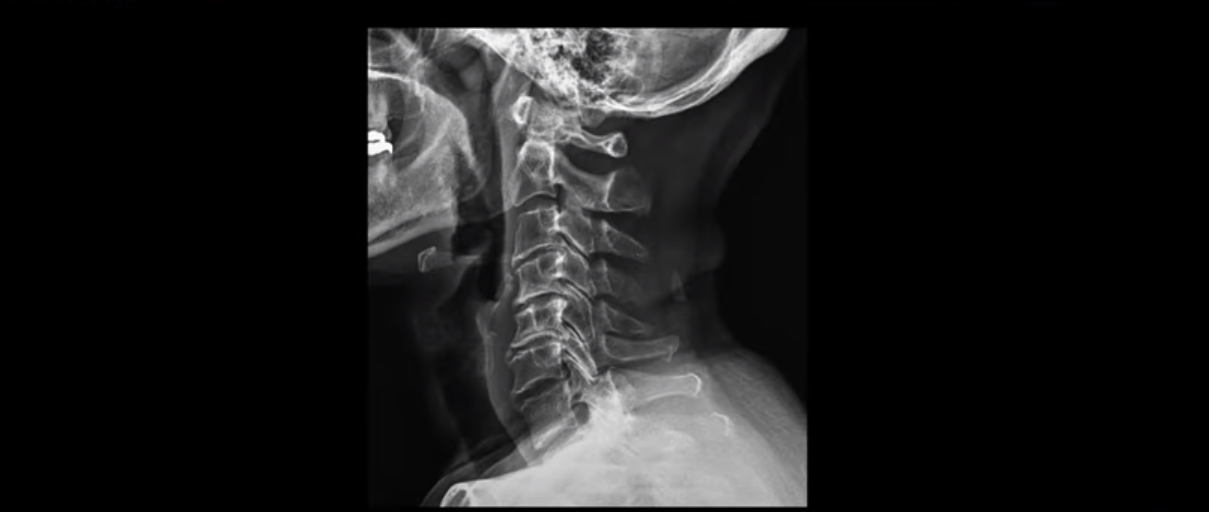

X-ray 보시다시피 완전 일자목 거북목에다 여러 마디가 전부 다 퇴행이 심하며

뼈 모양의 변형도 매우 심합니다.

이 환자분도 아까 X-ray에서 보여드렸듯이 아주 심한 일자목, 거북목이 있고 그 결과로 목의 거의 모든 마디가 다 퇴행이 진행되어 있죠. 즉 거북목은 모든 목질환, 특히 목디스크, 목협착증의 어머니 질환이며 그래서 목디스크를 치료하기 위해서는 반드시 거북목 때문에 짧아지고 뭉치고 굳고 뒤틀린 목 주변 근육들을 잘 치료해줘야 합니다.